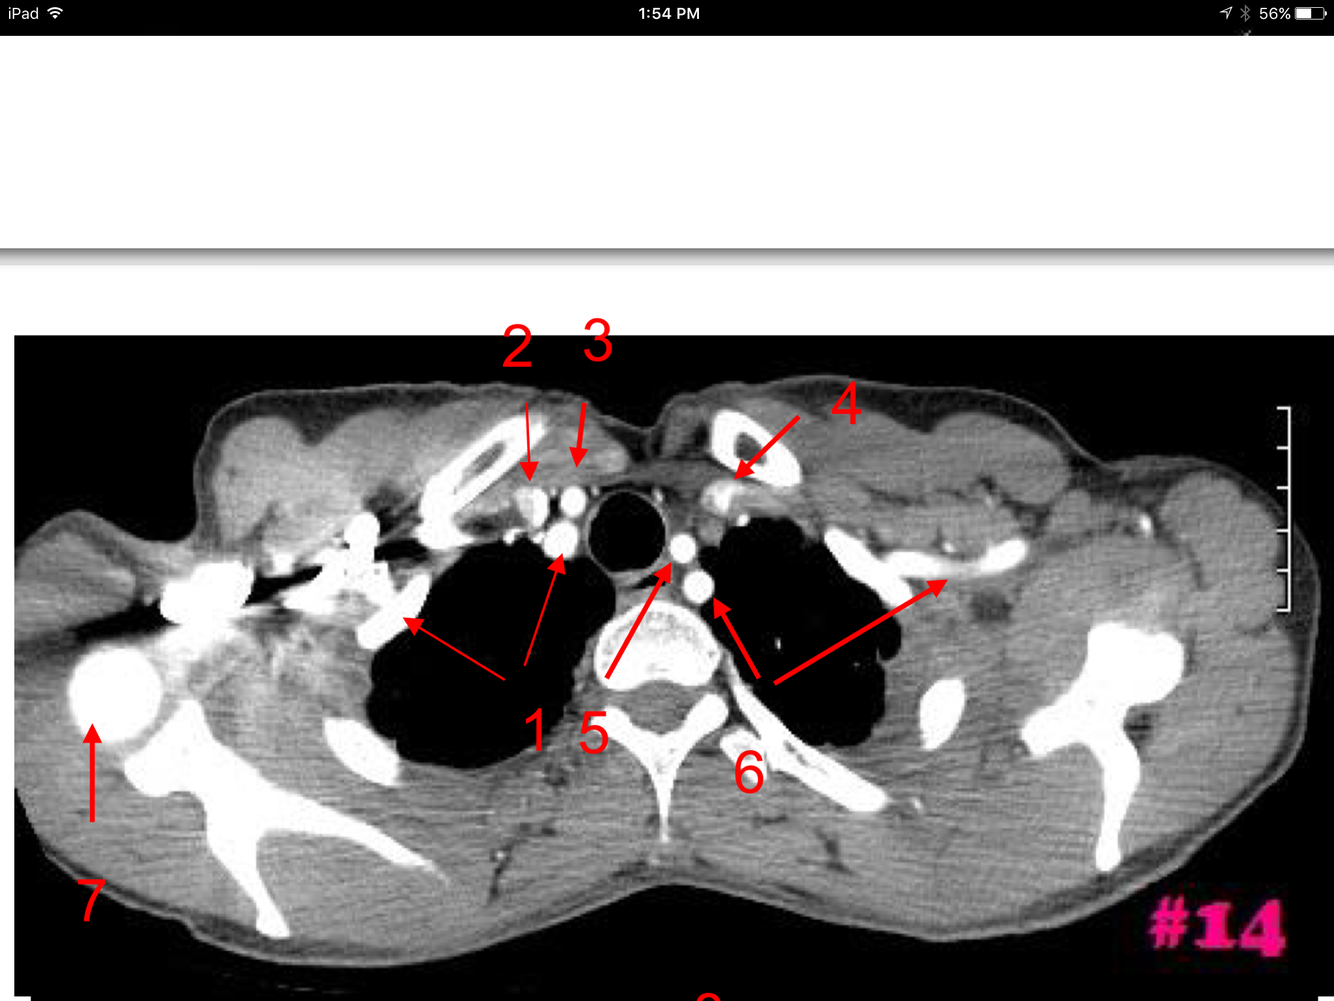

4

Q

A

Rt brachiocephalic vein

Lt brachiocephalic vein

Brachiocephlaic artery

Lt common carotid artery

Lt subclavian artery

Spine of the Rt scapula

Sternal end of Lt clavicle

How well did you know this?